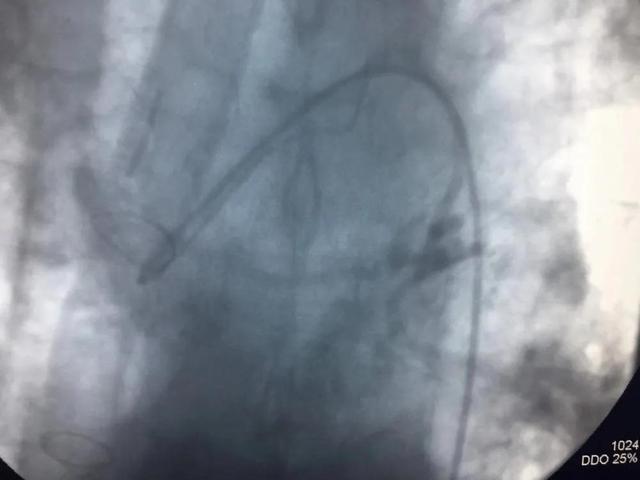

手术进行了2个小时,术中造影可见患者左、右支气管动脉、隔动脉、肋间动脉等多支血管异常增粗、迂曲、远端可见出血病灶;左上肺动脉分支末端见假性动脉瘤,是出血的“罪犯血管”,即行支气管动脉栓塞和肺动脉假性动脉瘤栓塞术。术后患者咯血停止,无并发症及不良反应发生,手术获得了满意的效果。